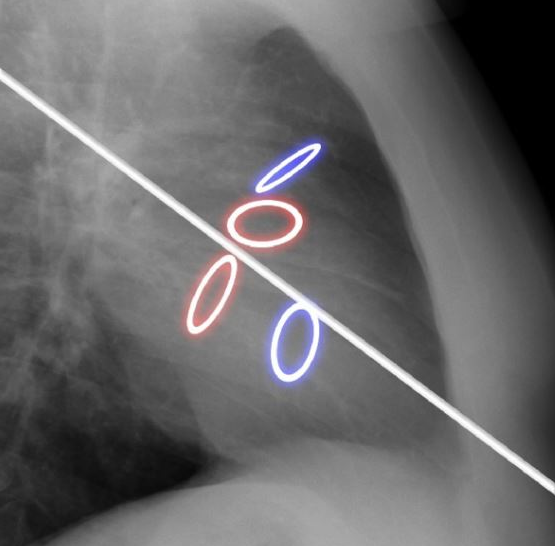

St-jude

Starr-Edwards (mirtale) et Bjork-Shiley (aorte)

Carpentier-Edwards (a), Ionescu-Shiley (b)